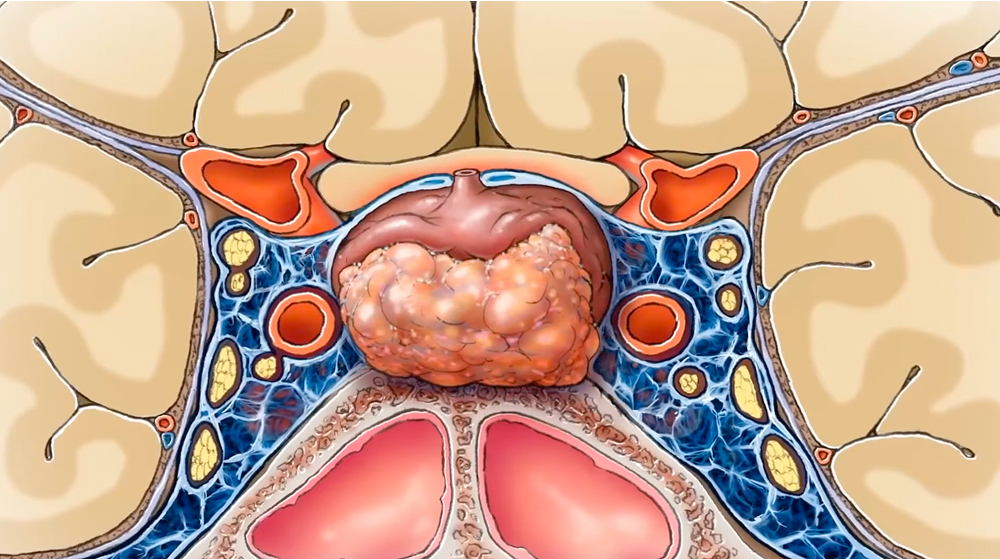

Los adenomas hipofisarios son tumores generalmente benignos localizados en la silla turca, aunque puede haber tumores invasores que se extienden más allá y dificultan su tratamiento.

La silla turca es una estructura ósea que aloja la glándula hipófisis y que, como su nombre lo indica, cuando es vista lateralmente, asemeja una silla de montar. La importancia de esta estructura radica en su cercanía con estructuras neurovasculares. Esta relación es crucial, ya que el crecimiento de un tumor hipofisiario causa frecuentemente la compresión de los nervios ópticos y produce un defecto visual caracterizado por la pérdida de la visión periférica. En algunos casos, el crecimiento de estos tumores puede invadir el seno cavernoso y los nervios que permiten la movilidad de los ojos.

Existen microadenomas (menores a 1 cm) y macroadenomas (mayores a 1 cm). La estrecha relación con estructuras neurovasculares es muy importante para determinar la posición de los tumores pituitarios.

Los macroadenomas tienen mayor posibilidad de desplazar los nervios ópticos y producir síntomas en el paciente.